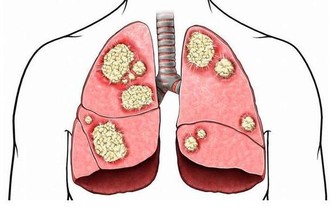

咳出有色的黏液咳嗽總是不痊癒,並生成粉紅色或白色的黏液(液體積聚在肺中),是心臟病的一個常見警告信號。即使看起來像是嚴重的感冒,也要盡快看醫生,以確保它不是更嚴重的問題。